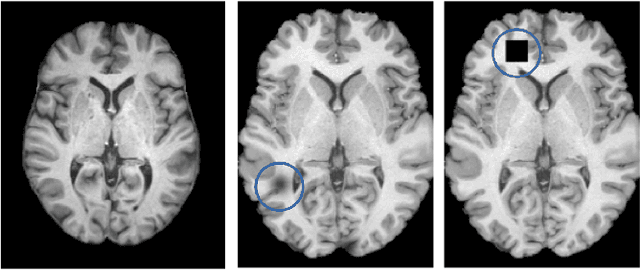

Abstract:Machine learning-based imaging diagnostics has recently reached or even superseded the level of clinical experts in several clinical domains. However, classification decisions of a trained machine learning system are typically non-transparent, a major hindrance for clinical integration, error tracking or knowledge discovery. In this study, we present a transparent deep learning framework relying on convolutional neural networks (CNNs) and layer-wise relevance propagation (LRP) for diagnosing multiple sclerosis (MS). MS is commonly diagnosed utilizing a combination of clinical presentation and conventional magnetic resonance imaging (MRI), specifically the occurrence and presentation of white matter lesions in T2-weighted images. We hypothesized that using LRP in a naive predictive model would enable us to uncover relevant image features that a trained CNN uses for decision-making. Since imaging markers in MS are well-established this would enable us to validate the respective CNN model. First, we pre-trained a CNN on MRI data from the Alzheimer's Disease Neuroimaging Initiative (n = 921), afterwards specializing the CNN to discriminate between MS patients and healthy controls (n = 147). Using LRP, we then produced a heatmap for each subject in the holdout set depicting the voxel-wise relevance for a particular classification decision. The resulting CNN model resulted in a balanced accuracy of 87.04% and an area under the curve of 96.08% in a receiver operating characteristic curve. The subsequent LRP visualization revealed that the CNN model focuses indeed on individual lesions, but also incorporates additional information such as lesion location, non-lesional white matter or gray matter areas such as the thalamus, which are established conventional and advanced MRI markers in MS. We conclude that LRP and the proposed framework have the capability to make diagnostic decisions of...